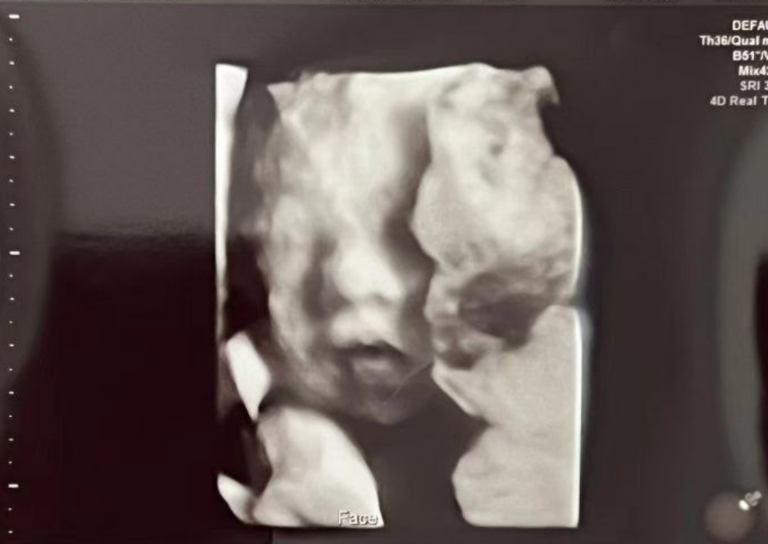

1月15日に四次元超音波(精密検査)を実施し、

異常は認められず、発育状況も順調であることが確認されました。

節目となる検査を無事に終え、母子ともに良好な状態です。